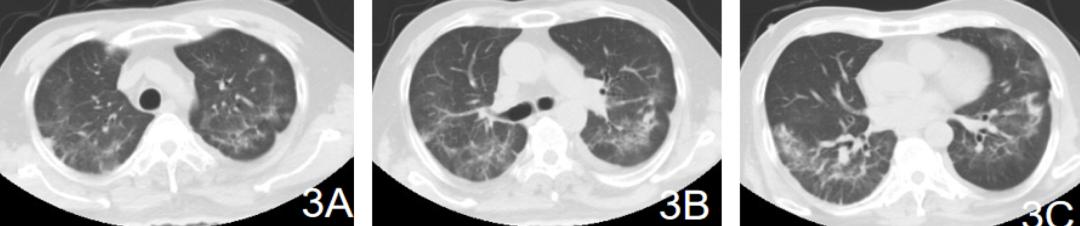

继续原治疗,3天后甲强龙40mg 由bid变为qd,3月18日复查肺CT肺部影像有吸收【图2】,呼吸困难缓解,动脉血氧恢复正常。血气分析:pH7.49 ,PO2 86mmHg,PCO2 35mmHg。停用甲强龙(共用6天),其他治疗不变,奥司他韦用药第7天停用。于3月23日复查肺CT,较入院时肺CT影像明显吸收【图3ABC】。

【图3】2020.3.23肺部CT较入院时缓解明显,距离图1间隔9天